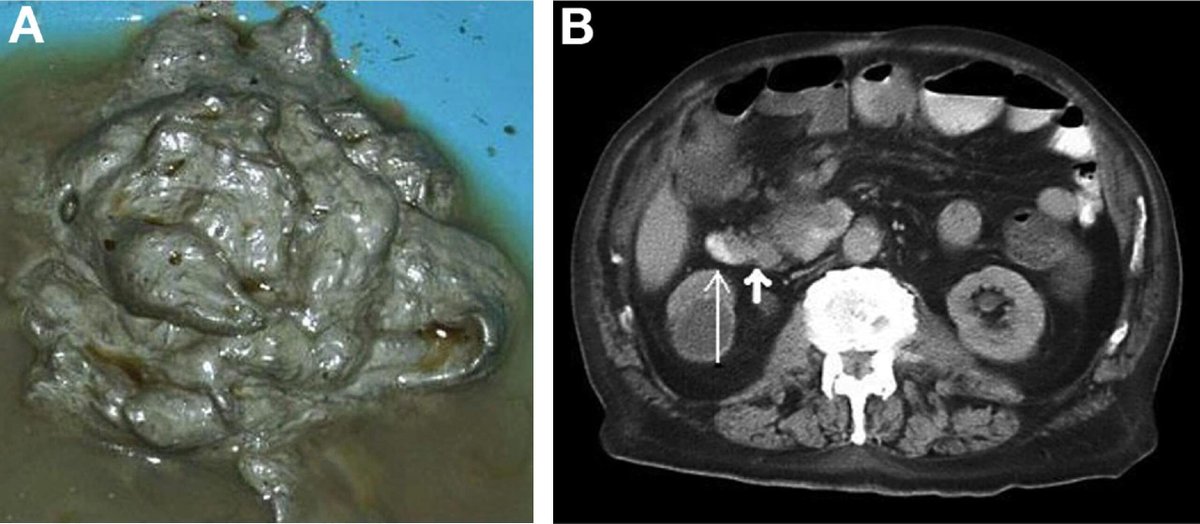

البراز الفضي #البراز_الفضي (علامة #توماس): مرض السرطان #السرطان #أمبولة_فاتر. كانت هذه الحالة #السرطان_القولون_المنتشر.

ما الذي يسبب لون #البراز_الفضي؟

يمكن أن يحدث البراز ذو اللون الفاتح (رمادي أو بلون الطين) عند البالغين بسبب نقص #الصفراء في الجهاز الهضمي. عادة ما يكون من انسداد في القنوات الصفراوية ، إما من حصوة أو ورم. تساعد الصفراء على هضم الدهون وهي مسؤولة عن اللون البني للبراز.